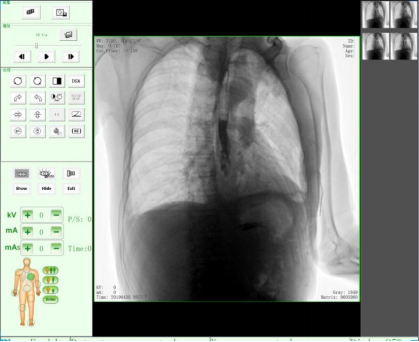

動態(tài)DR17*17英寸非晶硅動態(tài)平板探測器,透視像素達200萬,可實時顯示大幅面高清拍攝視野。適用于全身各部位攝影,包括常規(guī)攝影,如胸片、頸椎、腰椎、腹部、頭顱、四肢等,以及特殊攝影。

三、數(shù)字化透視

適用于全身各部位的透視檢查及輔助治療,如隱匿性肋骨骨折、胸透檢查、骨折復(fù)位、小兒腸套疊空氣灌腸等。同時具備多種幀率透視模式,影像更加流暢、準確。